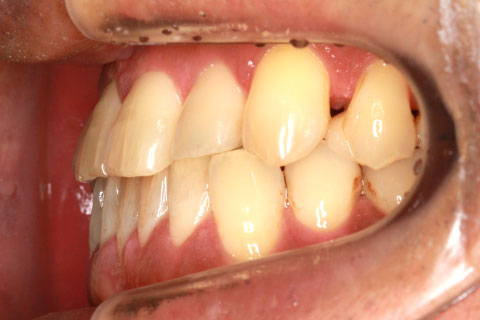

フルリンガル矯正2(上下の歯を舌側矯正で治療)

治療前

治療中

治療後

- 年齢・性別

- 42歳男性

- 治療期間

- 1年6ヶ月

- 抜歯

- なし

- 治療費

- 120万円(税込み)

- 備考

- マルチブラケットを用いた矯正治療

- 治療内容

- 反対咬合をフルリンガル矯正治療にて改善

- 施術の副作用(リスク)

- 表側矯正と比較して、歯根の角度を確立する「トルク」の力がかかりにくい。